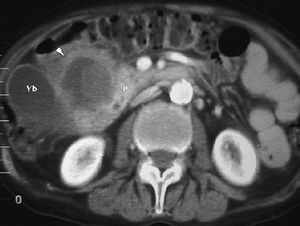

Una patología infrecuente es la fístula aortoduodenal, que se puede producir secundaria a un aneurisma de aorta en progresión o a procedimientos terapéuticos como la colocación de prótesis de aorta (fig. 15). En ocasiones puede observarse el paso de contraste de la aorta a la luz duodenal. Normalmente tiene una evolución fatal.

Fig. 15--Fístula aortoduodenal. Varón con hemorragia digestiva alta e imagen en tomografía computarizada con contraste intravenoso de aneurisma de aorta (*) que desplaza la luz duodenal (D) y con sangrado confirmado con endoscopia.